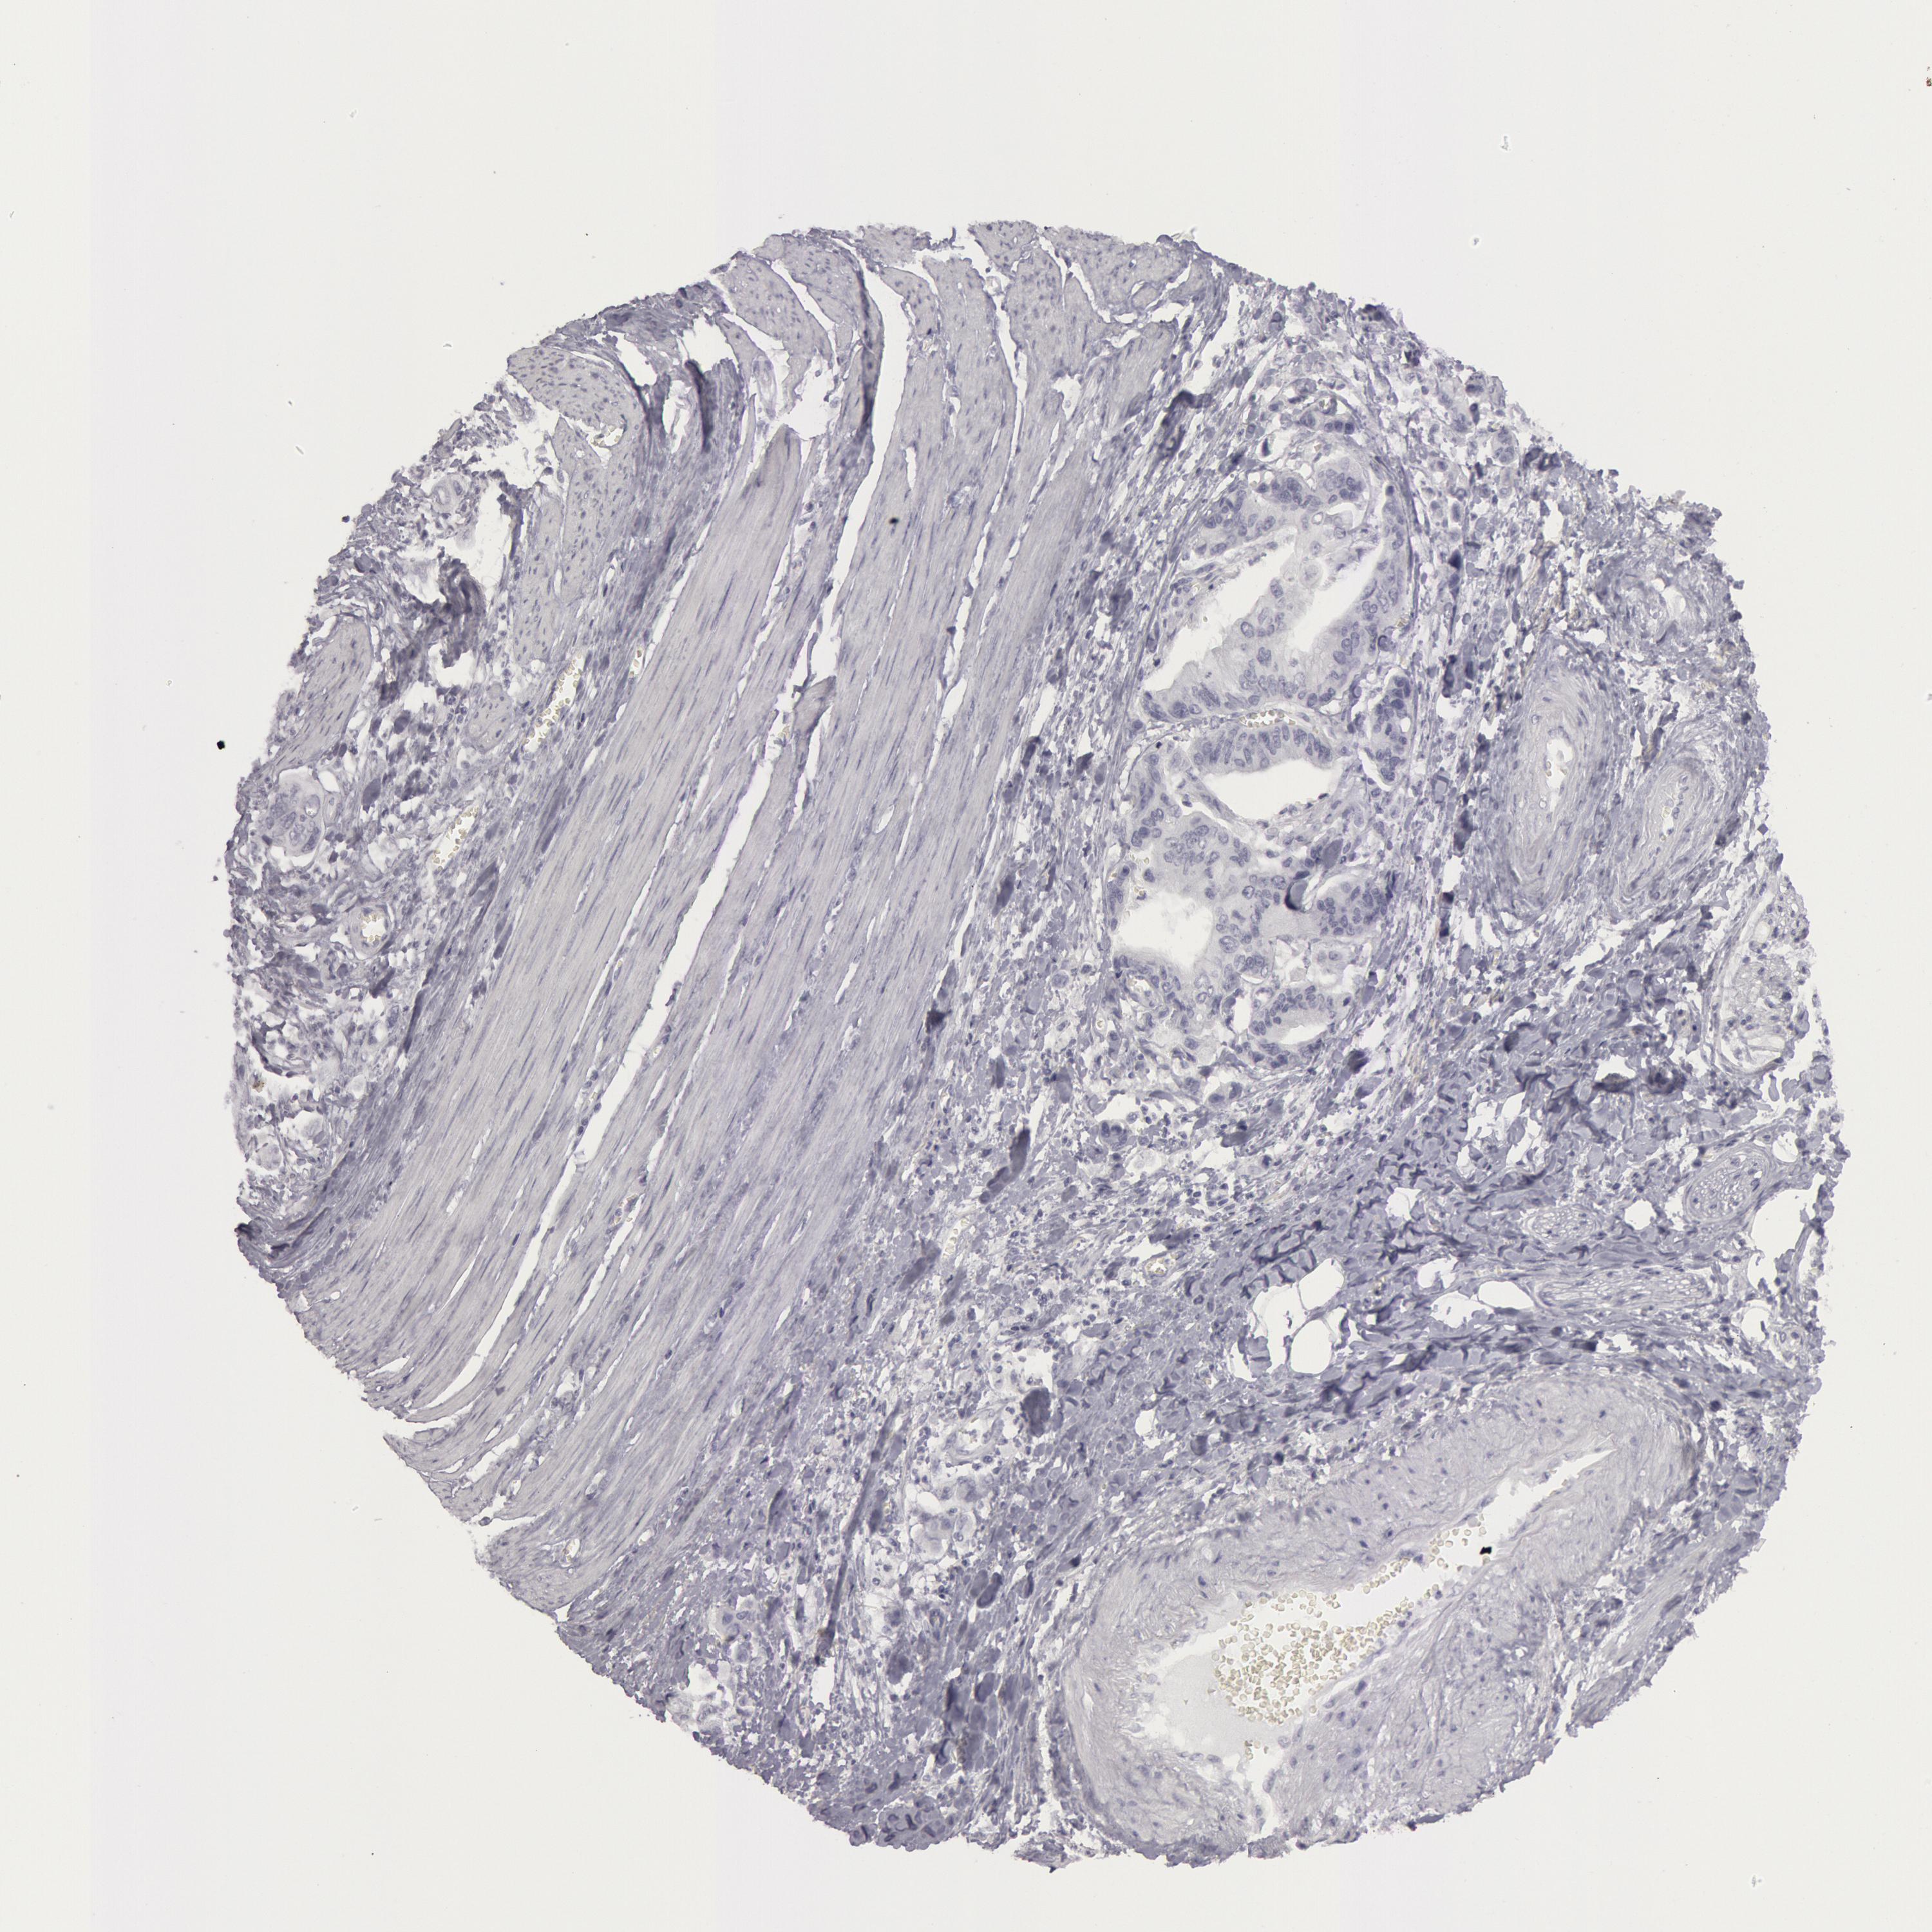

STOMACH CANCER - Protein expressioni

A mouse-over function shows sample information and annotation data. Click on an image to view it in a full screen mode. Samples can be filtered based on level of antibody staining by selecting one or several of the following categories: high, medium, low and not detected. The assay and annotation is described here.

Note that samples used for immunohistochemistry by the Human Protein Atlas do not correspond to samples in the TCGA dataset.

Antibody stainingi

Antibody staining in the annotated cell types in the current human tissue is reported as not detected, low, medium, or high, based on conventional immunohistochemistry profiling in selected tissues. This score is based on the combination of the staining intensity and fraction of stained cells.

Each image is clickable and will lead to virtual microscopy that enables deeper exploration of all samples and also displays staining intensity scores, fraction scores and subcellular localization as well as patient and tissue information for each sample.

Antibody CAB000136

Staining

High

Medium

Low

Not detected

Intensity

Strong

Moderate

Weak

Negative

Quantity

>75%

75%-25%

<25%

None

Location

Nuclear

Cytoplasmic/membranous

Cytoplasmic/membranous,nuclear

Adenocarcinoma, NOS